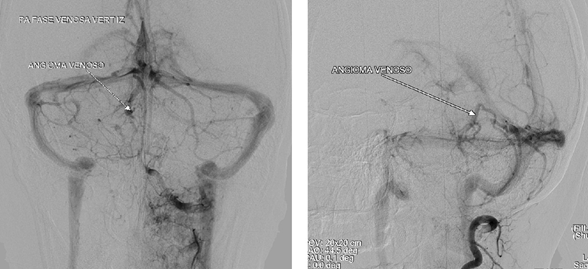

Given the recurrent symptomatology of the headache reported by the patient and the cavernoma found in the images, cerebral digital subtraction angiography (DSA) is recommended, in the arterial phase with no pathological findings (Figure 4) and the DVA in the territory evident in the venous phase. Right posterosuperior cerebellar with confluent drainage vein towards the straight sinus (Figure 5).

Figure 5 Digital subtraction angiography of the left vertebral artery in the venous phase showing the DVA with the “jellyfish head” sign on the right side (arrow) with a vein draining to the straight sinus.